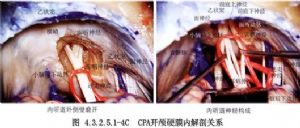

小腦橋腦角前界是顳骨巖部、巖上竇、三叉神經;外側面是巖骨錐體背面、內耳孔和乙狀竇;上方是小腦幕及小腦幕裂孔,中部有面神經與聽神經斜行通過。面神經長約2cm,聽神經瘤時,將面神經向前下擠壓,可拉長達4~5cm;前內側面爲橋腦與延髓,內後面爲小腦半球的側面,下面是舌咽、迷走、副神經,並有小腦下後動脈發出的小動脈支伴行(圖4.3.2.5.1-0-1)。

腫瘤生長過程中,向前推壓面神經與三叉神經。有時腫瘤巨大,可通過小腦幕裂孔向上生長入顱中窩。向內擠壓腦幹,超越中線。向下壓迫舌咽、迷走神經,尚可伸入枕骨大孔,個別者可長入頸內靜脈孔。內耳孔與內聽道多受破壞而擴大(圖4.3.2.5.1-0-2)。

腫瘤的供應動脈可來自小腦下前動脈、小腦下後動脈、內聽動脈,基底動脈有時直接向腫瘤發出供應支。腫瘤的引出靜脈匯入巖上竇、巖下竇。